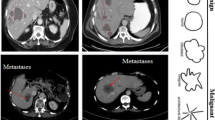

Deep learning (DL) is a recently developed artificial intelligent method that can be integrated into numerous fields. For the imaging diagnosis of liver disease, several remarkable outcomes have been achieved with the application of DL currently. This advanced algorithm takes part in various sections of imaging processing such as liver segmentation, lesion delineation, disease classification, process optimization, etc. The DL optimized imaging diagnosis shows a broad prospect instead of the pathological biopsy for the advantages of convenience, safety, and inexpensiveness. In this paper, we reviewed the published representative DL-related hepatic imaging works, described the general situation of this new-rising technology in medical liver imaging and explored the future direction of DL development.

Ben-Cohen A, Greenspan H. Liver lesion detection in CT using deep learning techniques. In: Handbook of Medical Image Computing and Computer Assisted Intervention, 2020; p. 65–90. https://doi.org/10.1016/B978-0-12-816176-0.00008-9

Ben-Cohen A, et al. Fully convolutional network for liver segmentation and lesions detection. Deep Learn Data Label Med Appl 2016. https://doi.org/10.1007/978-3-319-46976-8_9

Zhang Y, et al. Deep learning initialized and gradient enhanced Level-Set based segmentation for liver tumor from CT images. IEEE Access 2020;8:76056–76068